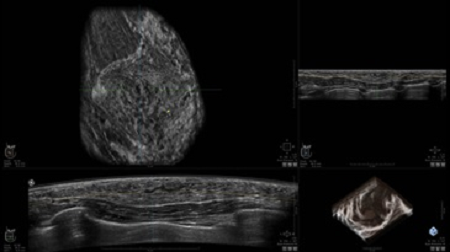

GE INVENIA ABUS – это современный УЗИ аппарат, который создан для точной и эффективной диагностики сканирования с высокой плотностью молочных желез. Выявляемость патологий раковых и предраковых стадий заболевания составляет 55%, что в конечном счете позволяет ставить врачу точные и своевременные диагнозы. Традиционные методы использования маммографии не показывают такой выявляемости, ограничиваясь лишь 3-38%.

УЗИ-аппарат GE INVENIA ABUS позволяет проводить максимально операторонезависимые процедуры, что значительно снижает риск неправильной постановки диагноза и сопутствующие издержки на обработку информации. Система готовит отчет в течение 3-х минут после сканирования, это безусловное преимущество по сравнению с обычным УЗИ сканером.

• Получение объемных 3D изображений с возможностью покадрового просмотра

• Получение изображений в поперечной плоскости (в реальном времени) и в коронарной плоскости (статическая, для указания нахождения соска)

• Отображение объемных 3D ультразвуковых изображений, которые состоят из традиционных поперечных и воссозданных коронарных и сагиттальных проекций

• Возможность отображения полного 3D изображения